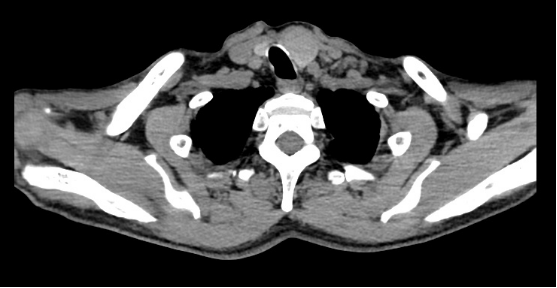

图3.术前CT形态学检查

病历回顾:患者男性,69岁,因发现甲状腺肿物1月入院。查体:颈前皮肤表面无红肿及皮肤破溃,甲状腺左叶可触及肿大结节,约3x2.5cm大小,质韧,随吞咽上下活动,活动度好,境界清,轻触痛。右叶未及明显肿大,外彩超示:甲状腺左叶囊实性结节,TI-RADS 3类。患者及家属有强烈颈部无瘢痕美容手术意愿,术前化验、甲功、甲状旁腺激素正常,心彩超、血气、肺功能正常。